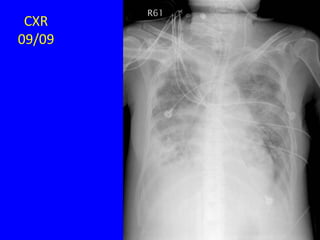

CXR of Bronchiectasis

Hansell DM - Radiol Clin North Am - 01-JAN-1998; 36(1): 107-28

• CXR

– Linear atelectasis, tram track, ring

shadow, irregular peripheral opacities